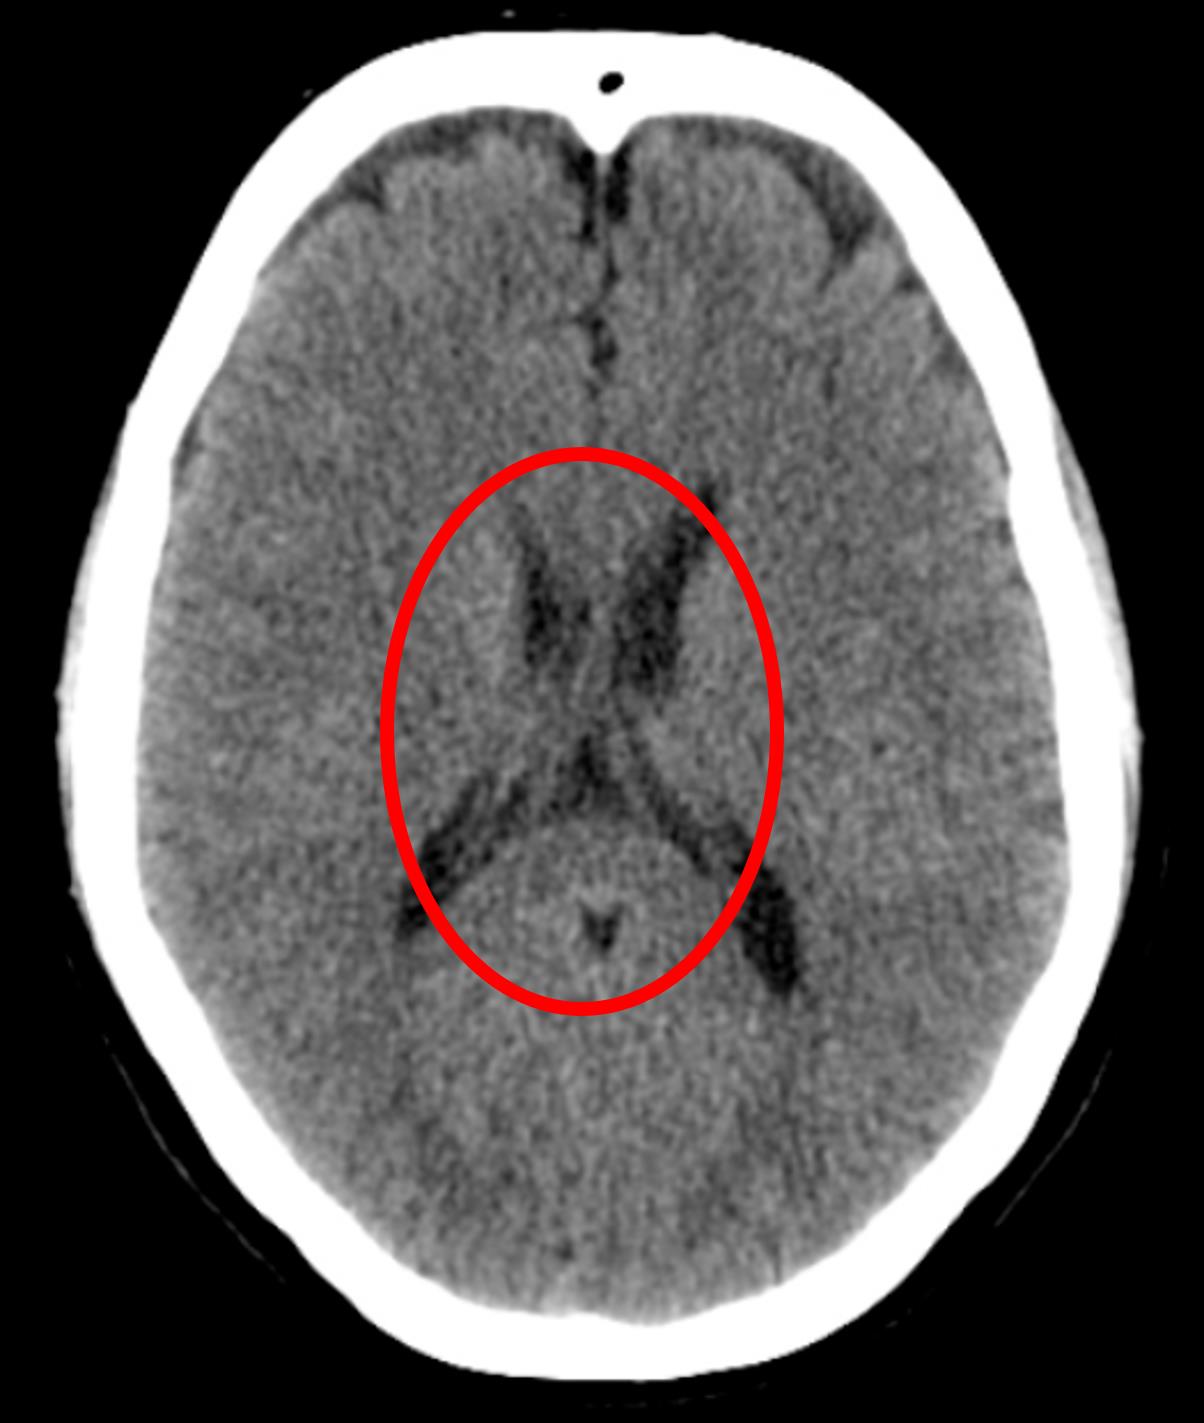

He has no symptoms at this time. His temperature is 99.5°F (37.5°C), pulse is 95/min, blood pressure is 129/70 mmHg, respirations are 10/min, and oxygen saturation is 98% on room air. A head CT is performed, and the results are shown in Figure A. Which of the following is the most appropriate next step in management?

Figure/Illustration A is a head CT demonstrating normal brain morphology with patent ventricles (red circle). This finding is consistent with SIADH due to a concussion.